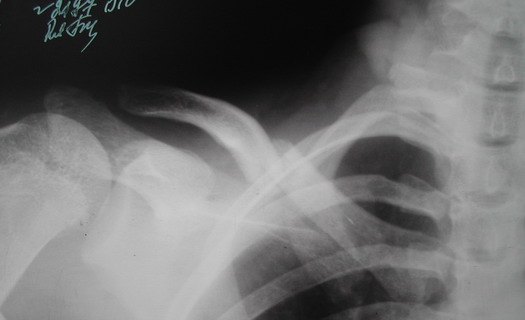

Во время стажировки в Австрии не мог не поинтересоавться, как австрийские хирурги лечат переломы ключицы. Оказалось, при переломах без смещения или с небольшим смещением накладывают восьмиобразную повязку, в остальных случаях выполняют остеосинтез пластинами.

Однако, чтобы уснуть с аппаратом внещней фиксации на ключице нужно "устать" не меньше, чем в рамке Чижина. К тому же, у некоторых больных присутсвует страх, что что-то в аппарате может раскрутиться, зацепиться за одеяло или подушку, или воспалиться. Крепко спят пациенты после качественного стабильного погружного остеосинтеза, когда ничего не торчит на коже. Особенно сладко спится после принятия душа или ванны. Это возможно после снятия швов. А вот у "чижиков" и "аппаратчиков" с полноценными водными процедурами определенные трудности.